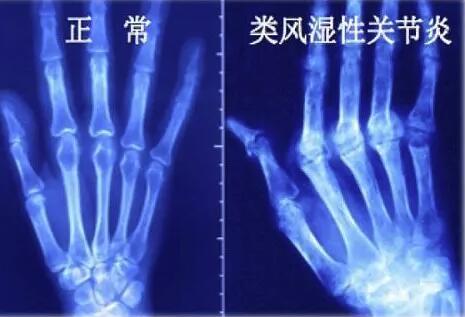

(1)美国风湿病学会1987年修订的RA分类标准如下≥4条可以确诊RA。①晨僵至少1小时(≥6周)。②3个或3个以上的关节受累(≥6周)。③手关节(腕、MCP或PIP关节)受累(≥6周)。④对称性关节炎(≥6周)。⑤有类风湿皮下结节。⑥X线片改变。⑦血清类风湿因子阳性(滴度>1:32)。

(2)病情分期①早期有滑膜炎,无软骨破坏。②中期介于上、下间(有炎症、关节破坏、关节外表现)。③晚期已有关节结构破坏,无进行性滑膜炎。